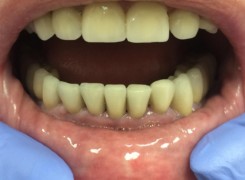

Pan Kamil zgłosił się do gabinetu po wypadku rowerowym w wyniku którego wybił ząb – lewą górną jedynkę. W takiej sytuacji została podjęta decyzja o implantacji natychmiastowej oraz zapatrzeniu pacjenta na czas integracji wszczepu w uzupełnienie tymczasowe.

Poniżej przebieg odbudowy protetycznej.